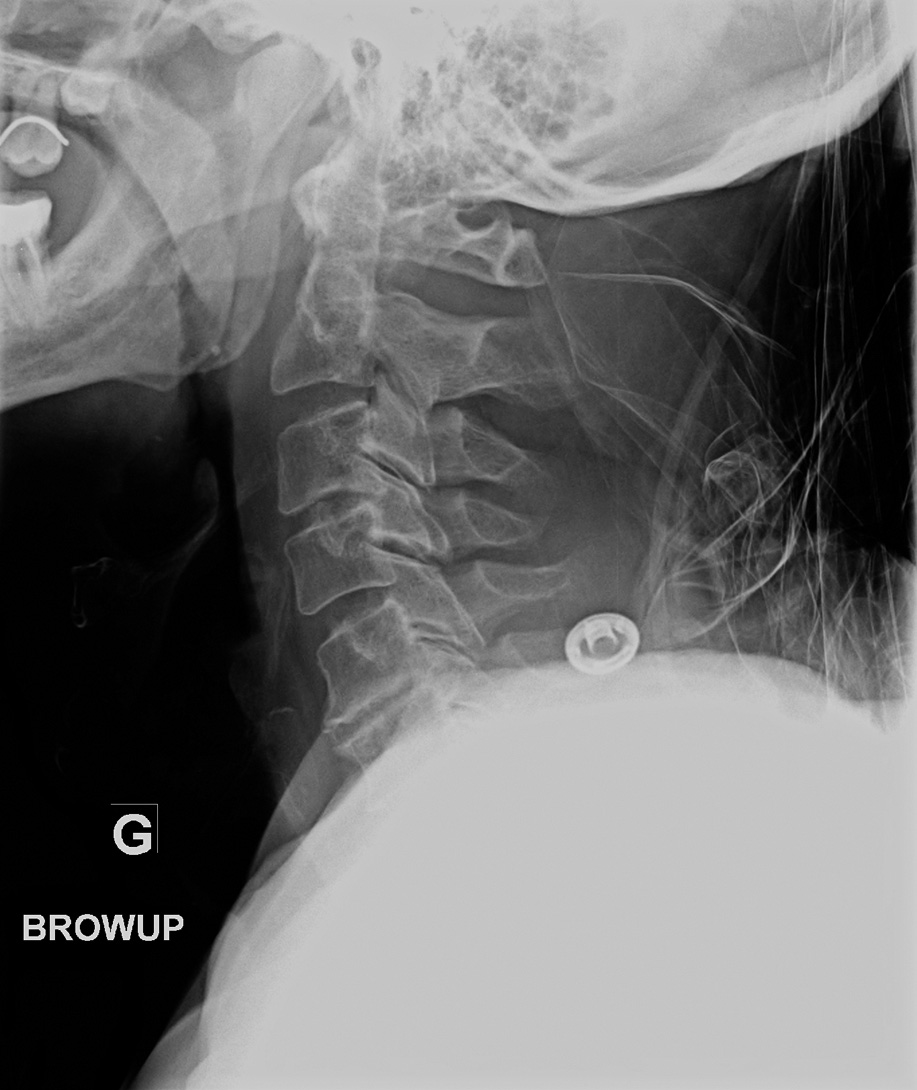

96-year-old female:

Cervical pain following a fall down the stairs.

Odontoid type 3 fracture located slightly below the odontoid waist and involving the body and lateral masses of C2.

C5-C6 disc degeneration with significant intersomatic height loss and anterior osteophytes.

Lateral